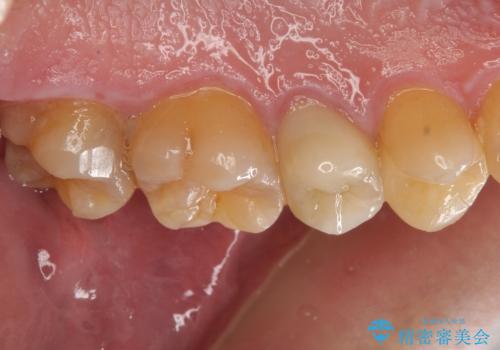

放置していた虫歯 セラミックインレーによる治療

- 食事の際に右上の奥歯が痛むので診てほしいとのことで来院。

視診では明らかに食べ物が詰まっているのがわかり、レントゲン写真では大きな虫歯の像が確認されました。

虫歯の大きさ次第でクラウンかインレーのどちらかになるだろうとご説明させていただき、今回はセラミックインレーでの治療となりました。